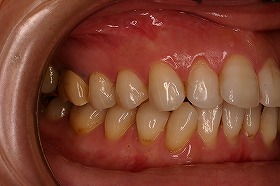

あまり歯のズレが少ないように見える方なのですが、

実は上下の前歯にがたつきがあり、

内側に歯が入り込んでしまっている症例です。

原因としては、あごが小さかったり、

アゴに対して歯が大きい場合など、

歯の生える場所が足りない時に起こります。